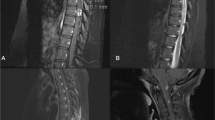

Sarcoidosis is a multi-system, non-caseating granulomatous disease of unknown etiology. Although spinal cord involvement is rare, it may cause severe neurological complications. We report the case of a 52-year-old woman who developed low back pain and a progressive flaccid paraparesis whose investigations revealed pulmonary and spinal sarcoidosis. To our knowledge, this is the first reported case of sarcoidosis of the conus medullaris and cauda equina diagnosed by an unusual enhancement pattern observed on magnetic resonance imaging with gadolinium. Biopsy of the lumbar nerve roots and of the lung revealed a non-caseating granuloma. Treatment with steroids and intensive rehabilitation resulted in remarkable functional improvement. Although rare, sarcoidosis of the conus medullaris and cauda equina should be considered in the differential diagnosis of flaccid paraparesis, particularly in patients with non-diagnostic evaluations.